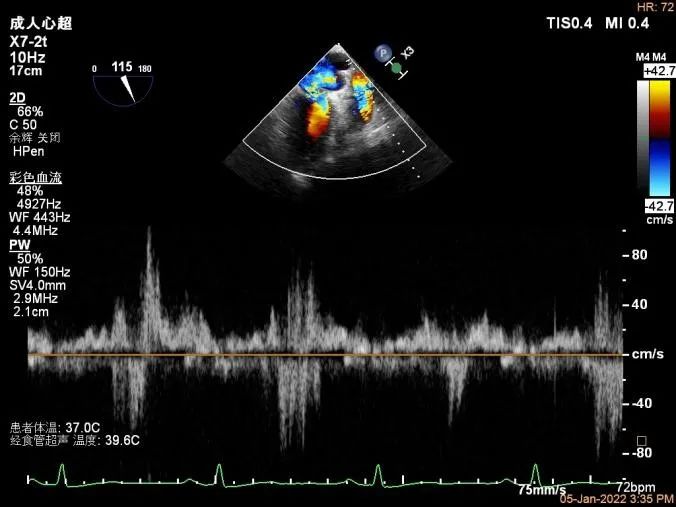

Bicom:MR(重度),返流束宽12mm,返流面积10.3cm2,PISA法定量EROA:

0.77cm2,Rvol:115ml,RF:35%,r:12mm。

二尖瓣返流频谱呈全收缩期

肺静脉血流频谱呈收缩期反向